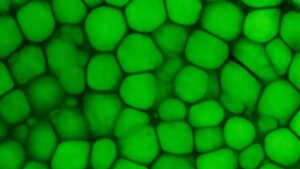

diverse Oamenii de știință descoperă un nou tip de cartilaj, care arată ca „Bubble Wrap” plin de grăsime 10 ianuarie 2025 by Echipa Club S&T | Leave a Comment Acesta este un tip de cartilaj nou descris, numit „lipocartilaj”. Această imagine arată țesut de la o ureche de șoarece cu bule de grăsime în celule colorate cu colorant verde. (Credit imagine: Plikus lab, Universitatea din California, Irvine) Oamenii de știință spun că au identificat un nou tip de cartilaj – unul care a fost […] Read more »